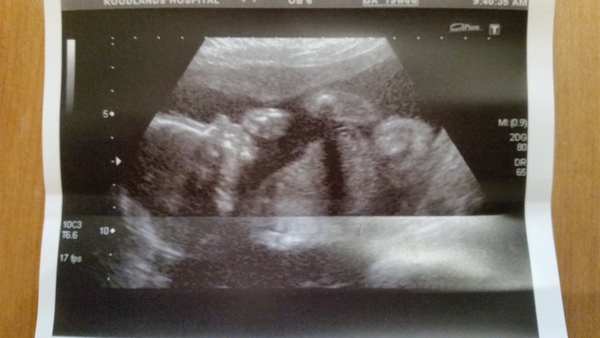

20w scan today and all measurements, organs etc all fine! Yahoo!

Oh wow, what a fab picture lily, can't wait to see ours next weds!

Even though I've got quite a bump now, I still can't comprehend that something 6 inches crown to rump is inside me, will be fab to see it, the 12w scan feels a lifetime ago now

lily great scan pic! Good news all is going well!